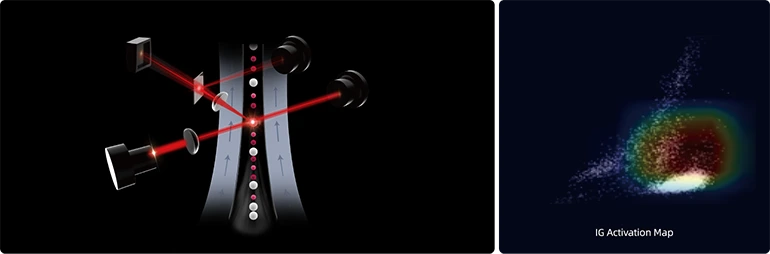

Передовая технология искусственного интеллекта для WBC

- Повысьте точность маркировки для Blast/IG.

- Комплексная и логичная процедура анализа ИИ для распространенных видов лейкемии, таких как ОМЛ и ОЛЛ.